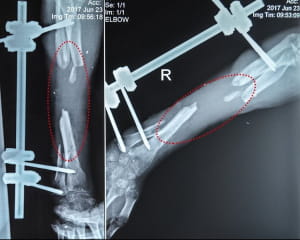

Унаслідок поранення Володимир має значні дефекти кісток передпліччя. Це практично неможливо якісно вилікувати за допомогою загальноприйнятих методик, додають у People`s Project.

"Крім того, вогнепальний остеомієліт прогресує та невпинно погіршує ситуацію: збільшує дефект кісткової тканини і з часом може призвести до втрати руки. Реконструктивно-відновлювальне лікування із застосуванням клітинних технологій допоможе подолати остеомієліт, компенсувати дефект та відновити цілісність кісток і, зрештою, максимально повернути функції руки", - наголошують волонетри.